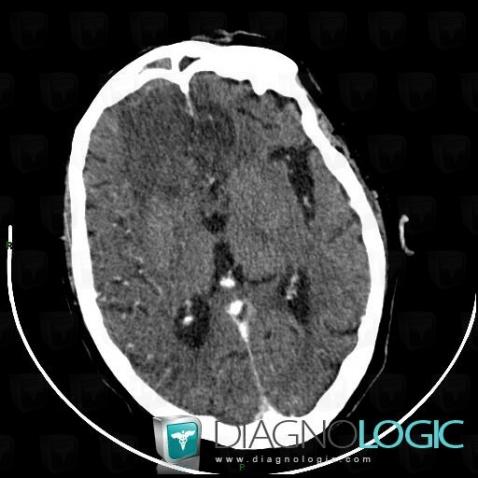

Abscess, Cerebral hemispheres, CT

Here is the specific information in the key image above:

- Diagnosis Abscess, Location(s) Cerebral hemispheres, with gamuts Intracerebral mass, Intracerebral lesion with ring enhancement, Multifocal intracranial lesions, Intracerebral lesion with moderate enhancement